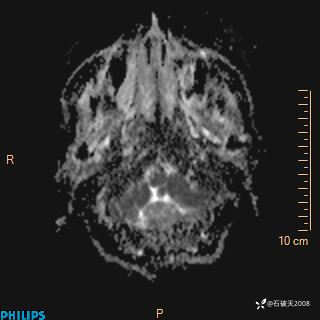

ADC